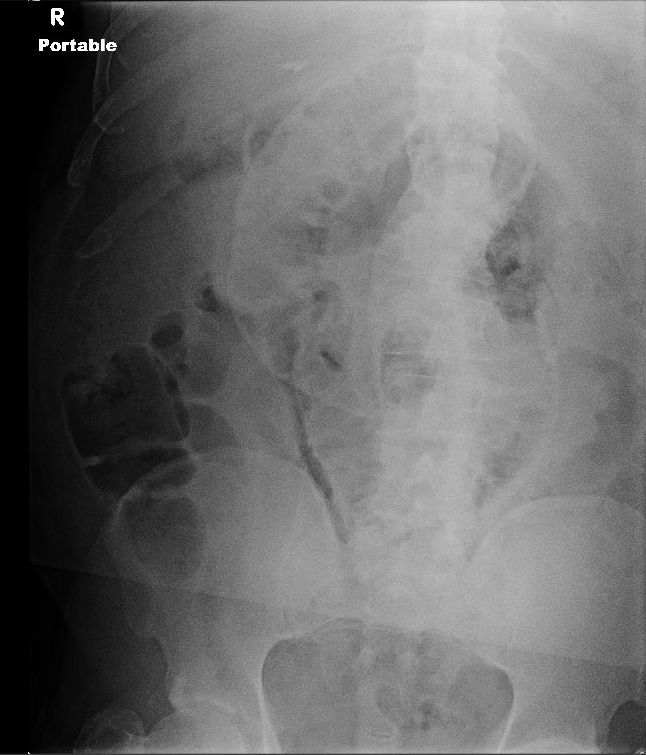

Learning Radiology retained, surgical, sponge, gossypiboma, foreign Sponge Foreign Body Unintended retention of a foreign object (urfo) is the broadest term and can include other items left in a patient at the time of a. The purpose of this study was to describe reports of unintentionally retained surgical sponges (rss): Prevention of unintentionally retained surgical items after surgery requires good communication among perioperative personnel. The retention of a foreign object. Sponge Foreign Body.

Foreign Body & Radiopaque Surgical Items on Film Sponge Foreign Body A gossypiboma, also called textiloma or cottonoid, refers to a foreign object, such as a mass of cotton matrix or a sponge, that is left. The retention of a foreign object may cause serious patient harm and often requires further medical treatment. Clinically, retained sponges may be asymptomatic or result in a granulomatous response with abscess development, intestinal obstruction, or. Sponge Foreign Body.

Imaging of Retained Surgical Sponges in the Abdomen and Pelvis AJR Sponge Foreign Body A retained surgical sponge or swab is also known as a gossypiboma, derived from gossypium (latin, cotton) and boma (swahili, place of concealment). A gossypiboma, also called textiloma or cottonoid, refers to a foreign object, such as a mass of cotton matrix or a sponge, that is left. The purpose of this study was to describe reports of unintentionally retained. Sponge Foreign Body.